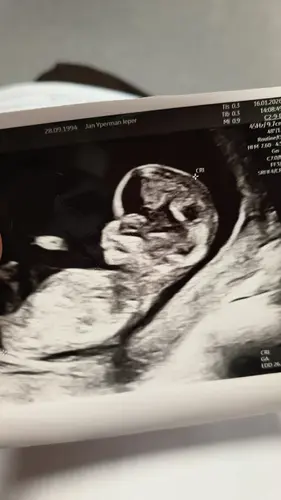

Vandaag exact 12w! 🤩

13 weken vandaag🥰 echo van vorige week een vrolijk rond stuiterend baby’tje 🙈